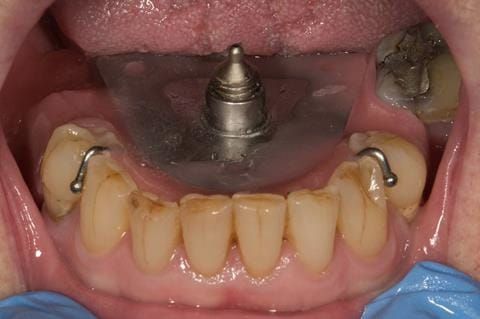

- Poorly fitting cobalt chromium based maxillary partial denture, which has been added to. This exhibited poor retention, stability and tissue fit (support). Unable to wear a new acrylic based denture.

Following consultation and second discussion appointment the patient chose to have option 2 namely, a window denture - maxillary cobalt chromium based partial denture. The clinical situation and treatment process is shown in detail below with photographs. The patient was successfully rehabilitated with this and her quality of life considerably improved. The clinical work was provided by Finlay and the technical work by Rowan.